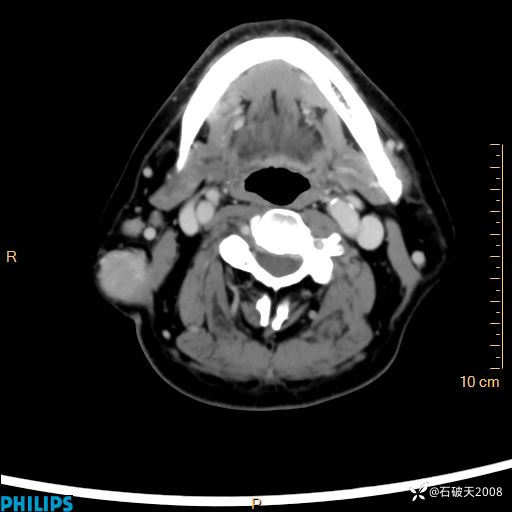

病例分享:颈部占位,一周后公布病理

男 57岁 主 诉:发现右侧颌下肿物1月余。

现病史:1月余前家属发现右侧颌下肿物。局部皮肤无红肿、热痛,无吞咽困难,无异物感,无恶心、呕吐,无头痛、头晕,无胸闷、胸痛,无发热、咳嗽、咳痰及呼吸困难。于我院行体表肿块彩超检查(2024.03.15我院)示:右侧耳下皮下软组织内低回声,未治疗。今为进一步治疗门诊以“腮腺肿瘤”为诊断收住我科,发病来患者神志清,精神可,饮食、睡眠及大小便正常,体重无明显下降。

动脉期